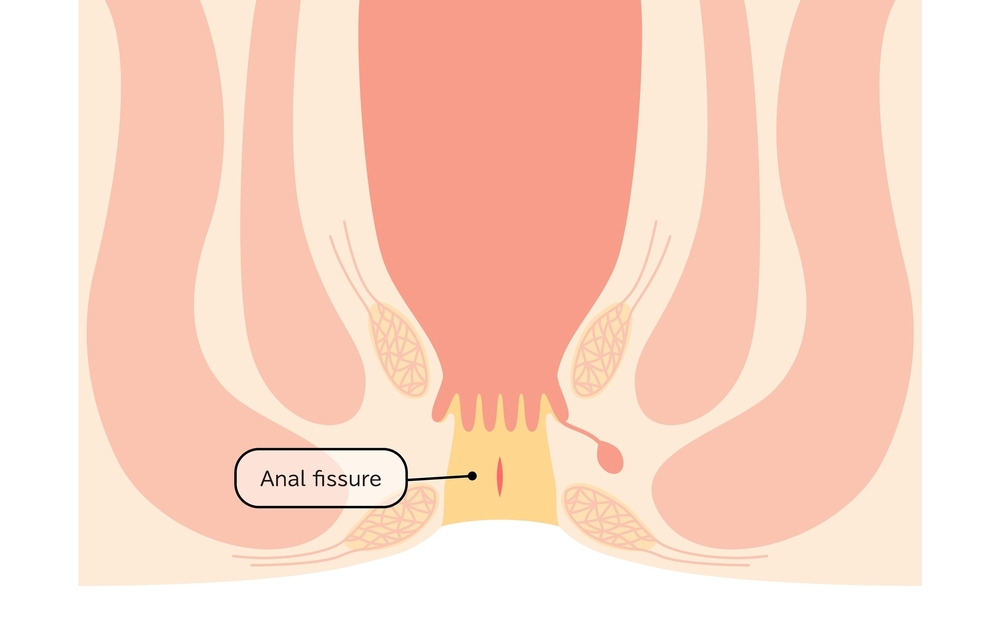

زخم شقاق؛ پیامد نادیده گرفتن یبوست

یبوست مزمن، اگر بهموقع درمان نشود، میتواند عوارض دردناکی در ناحیه مقعد ایجاد کند که یکی از شایعترین آنها «شقاق» یا فیشر مقعدی است. شقاق به ترک یا بریدگی سطحی در دیواره داخلی کانال مقعد گفته میشود که معمولاً در اثر عبور مدفوع خشک، حجیم یا با فشار زیاد ایجاد میشود.

این زخم کوچک اما حساس، میتواند باعث درد شدیدی در هنگام دفع و حتی پس از آن شود. برخلاف هموروئید که بیشتر با خونریزی بدون درد همراه است، شقاق اغلب با درد تیر کشنده، سوزش و گاهی اسپاسم عضلات اطراف مقعد بروز میکند و در موارد شدید، میتواند منجر به ترس بیمار از اجابت مزاج و در نتیجه، تشدید یبوست شود؛ این چرخه معیوب اغلب درمان را پیچیدهتر میکند.

نقش یبوست در بروز شقاق

در حالت طبیعی، بافت مقعد خاصیت انعطافپذیری دارد، اما زمانی که مدفوع خشک و سفت به دفعات از این ناحیه عبور میکند، فشار بیش از حد باعث ایجاد ترکهای میکروسکوپی یا زخمهای سطحی میشود. تکرار این حالت یا دفع همراه با زور زدن زیاد، میتواند این ترکها را به زخمهای مزمن و دردناک تبدیل کند.

علائم شقاق مقعدی

علائم این عارضه معمولاً بهوضوح قابل تشخیص است:

درد تیز و بریدگیمانند هنگام دفع

سوزش و خارش پس از اجابت مزاج

مشاهده مقدار کمی خون روشن روی مدفوع یا دستمال

احساس اسپاسم یا انقباض عضلات مقعد

در موارد مزمن، ایجاد زائده پوستی یا “منگوله” در اطراف ترک

۲. شقاق مقعدی (فیشر)

فشار زیاد حین دفع مدفوع خشک و سفت، ممکن است باعث ایجاد ترک یا زخم در دیواره مقعد شود. این زخمها دردناک، خونریزیکننده و مقاوم به درمانهای سطحی هستند. شقاق در بسیاری موارد باعث ترس از اجابت مزاج شده و یبوست را تشدید میکند.